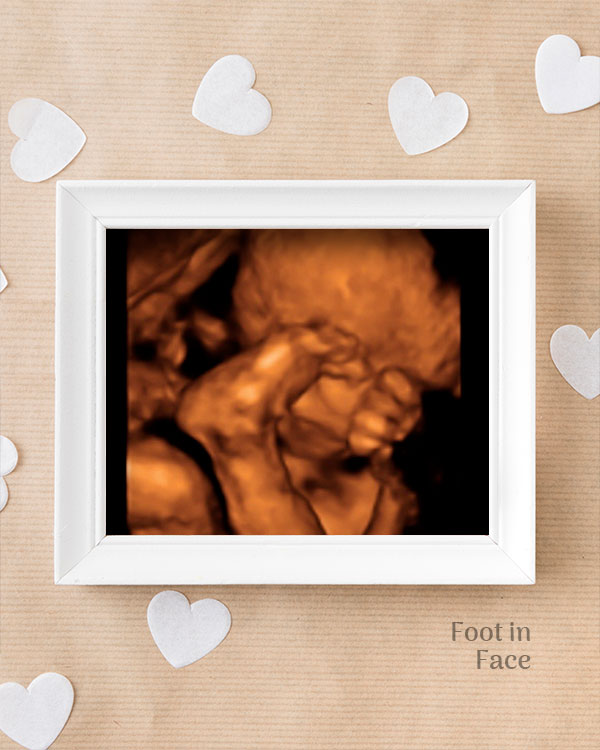

3D / 4D Baby Scan

Mediserv Diagnostics pioneered 4D scanning in the Malabar region. These advanced scans provide realistic images of the baby, allowing detailed evaluation of fetal structures and movements while creating a meaningful bonding experience for parents.